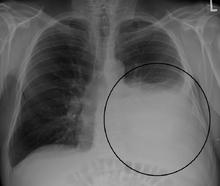

A large left sided pleural effusion as seen on an upright chest X-ray

A pleural effusion is usually diagnosed on the basis of medical history and physical exam, and confirmed by a chest X-ray. Once accumulated fluid is more than 300 mL, there are usually detectable clinical signs, such as decreased movement of the chest on the affected side, dullness to percussion over the fluid, diminished breath sounds on the affected side, decreased vocal resonance and fremitus (though this is an inconsistent and unreliable sign), and pleural friction rub. Above the effusion, where the lung is compressed, there may be bronchial breathing sounds and egophony. A large effusion there may cause tracheal deviation away from the effusion. A systematic review (2009) published as part of the Rational Clinical Examination Series in the Journal of the American Medical Association showed that dullness to conventional percussion was most accurate for diagnosing pleural effusion (summary positive likelihood ratio, 8.7; 95% confidence interval, 2.2–33.8), while the absence of reduced tactile vocal fremitus made pleural effusion less likely (negative likelihood ratio, 0.21; 95% confidence interval, 0.12–0.37).[6]

Imaging

A pleural effusion appears as an area of whiteness on a standard posteroanterior chest X-ray.[7] Normally, the space between the visceral pleura and the parietal pleura cannot be seen. A pleural effusion infiltrates the space between these layers. Because the pleural effusion has a density similar to water, it can be seen on radiographs. Since the effusion has greater density than the rest of the lung, it gravitates towards the lower portions of the pleural cavity. The pleural effusion behaves according to basic fluid dynamics, conforming to the shape of pleural space, which is determined by the lung and chest wall. If the pleural space contains both air and fluid, then an air-fluid level that is horizontal will be present, instead of conforming to the lung space.[8] Chest radiographs in the lateral decubitus position (with the patient lying on the side of the pleural effusion) are more sensitive and can detect as little as 50 mL of fluid. At least 300 mL of fluid must be present before upright chest X-rays can detect a pleural effusion (e.g., blunted costophrenic angles).